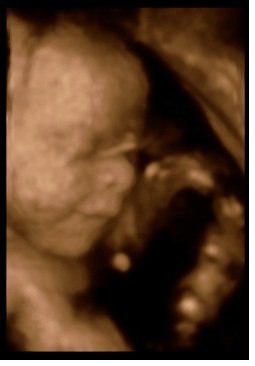

Jeg fik lavet en 3D scanning i 30+0 og fik nogle perfekte billeder. Vi har endda et hvor han smiler

Meget! Se her:

Vedhæftede fotos (klik for at se i fuld størrelse)

Meget! Både moren og faren måtte tude under scanningen. Han er så 6½ måneder nu og den dejligste lille dreng.